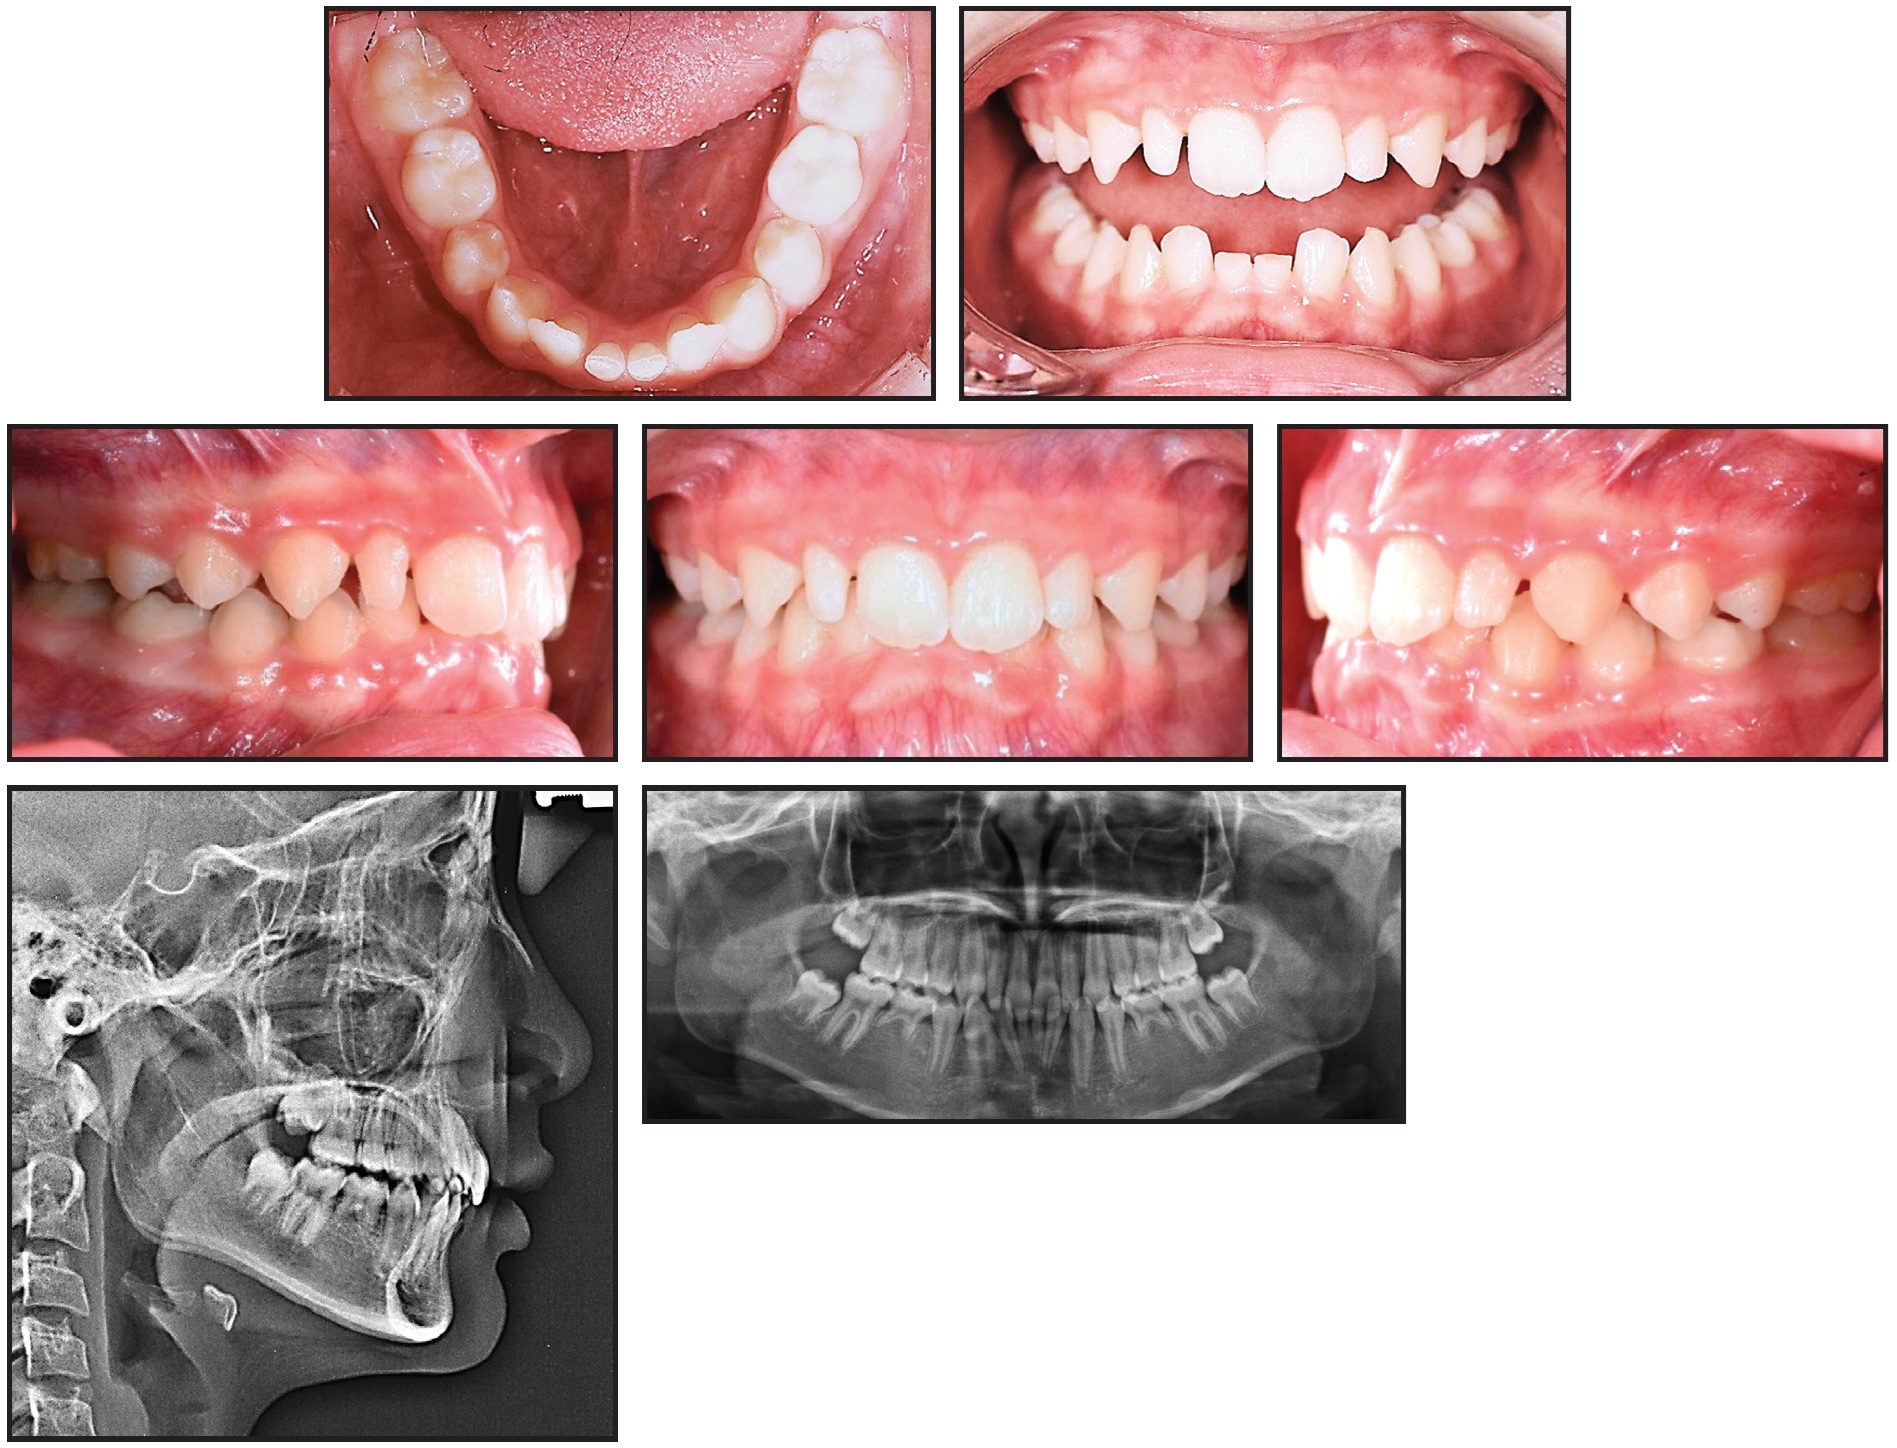

A 13-year-old female presented with an anterior deep bite, congenitally missing lower permanent central incisors and second premolars, and a skeletal Class II relationship (Fig. 4). We planned to use nonextraction treatment to correct the skeletal discrepancy.

Fig. 4 13-year-old female patient with anterior deep bite, congenitally missing lower permanent central incisors and second premolars, and skeletal Class II relationship before treatment.